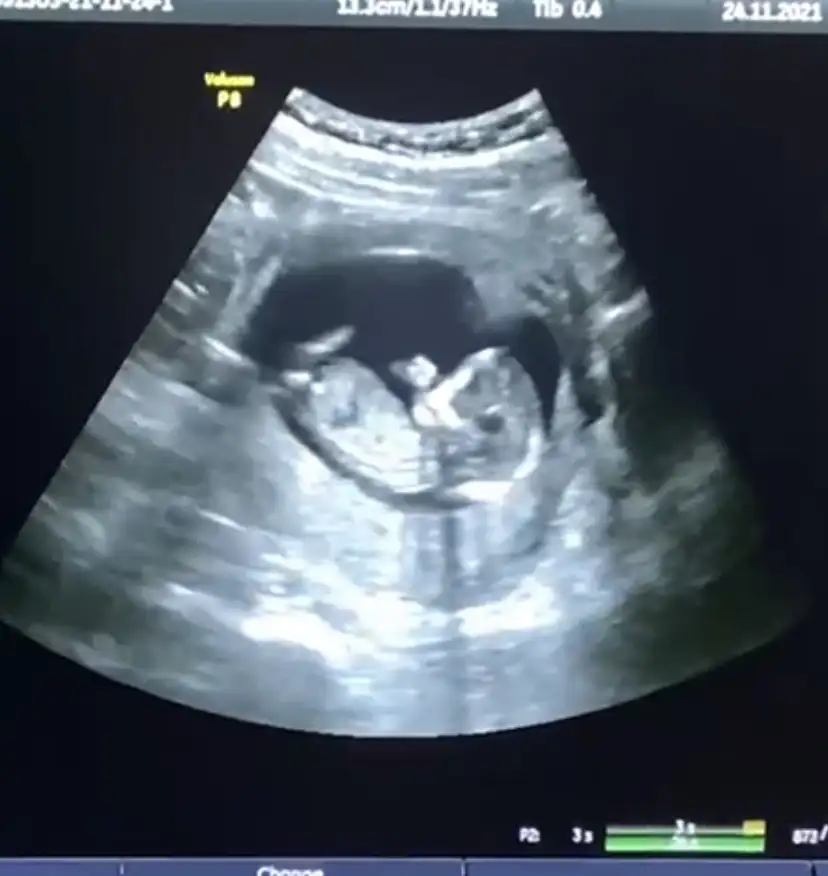

ben kontrolden çıktım, ikili test için kan alındı, sonuçları iki gün içinde çıkar denildi, detaylı kontrolde de ensesini vs ölçtüler, her şey yolundaymış, kan sonucu da çıkınca arayacaklar

fotolarda görüldüğü üzere parmak emenler kulübünden, aç kaldı yavrucak

%90 erkek dedi